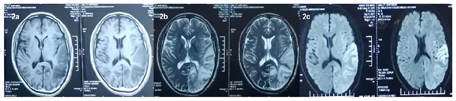

脑电图:中度异常脑电图(清醒闭目状态下,两半球枕区背景以6-7Hz的θ节律为主;较多广泛性中高波幅ð波短阵发放,以左侧蝶骨、中颞、额极、额略著,右侧蝶骨、前额、中颞、额极、额次之。)2021-09-24 ADC片2021-09-24 T2;

磁共振:磁共振灌注加权成像(PWI):左侧颞枕叶病灶区高灌注。磁共振波谱分析(MRS):左侧颞枕顶叶见大片状长T2信号,脑MRS示将体素置于左侧枕叶病变实性部位,Cho/cr值为1.17,NAA/cr=0.34,cho/NAA的值为3.38, Lac峰出现。(图7)

患者中年男性,反复卒中发作,伴有认知下降,外院以"病毒性脑炎"治疗效差,患者外院两次头颅磁共振提示左侧颞枕叶病变,第二次磁共振比第一次病灶面积增大,且磁共振提示病灶为分层样改变,患者发病来无四肢抽搐,根据病史及影像学定位为:大脑皮层、枕叶、左侧锥体束、左侧脊髓丘脑束,定性考虑:卒中?代谢性?炎性?感染?结合患者卒中样发作;影像学表现;认知障碍、血乳酸显著增高、磁共振波谱成像显示病灶、≥2次卒中样发作、患者母亲有糖尿病史、肌电图提示周围神经受累、体重下降、卒中样发作急性期病灶弥散加权成像(DWI)弥散受限,皮质受累尤为明显,呈现类花边征样改变。病灶具有进展性、可逆性、多发性以及呈现"此消彼长"的"游走性"特点[3,4]。